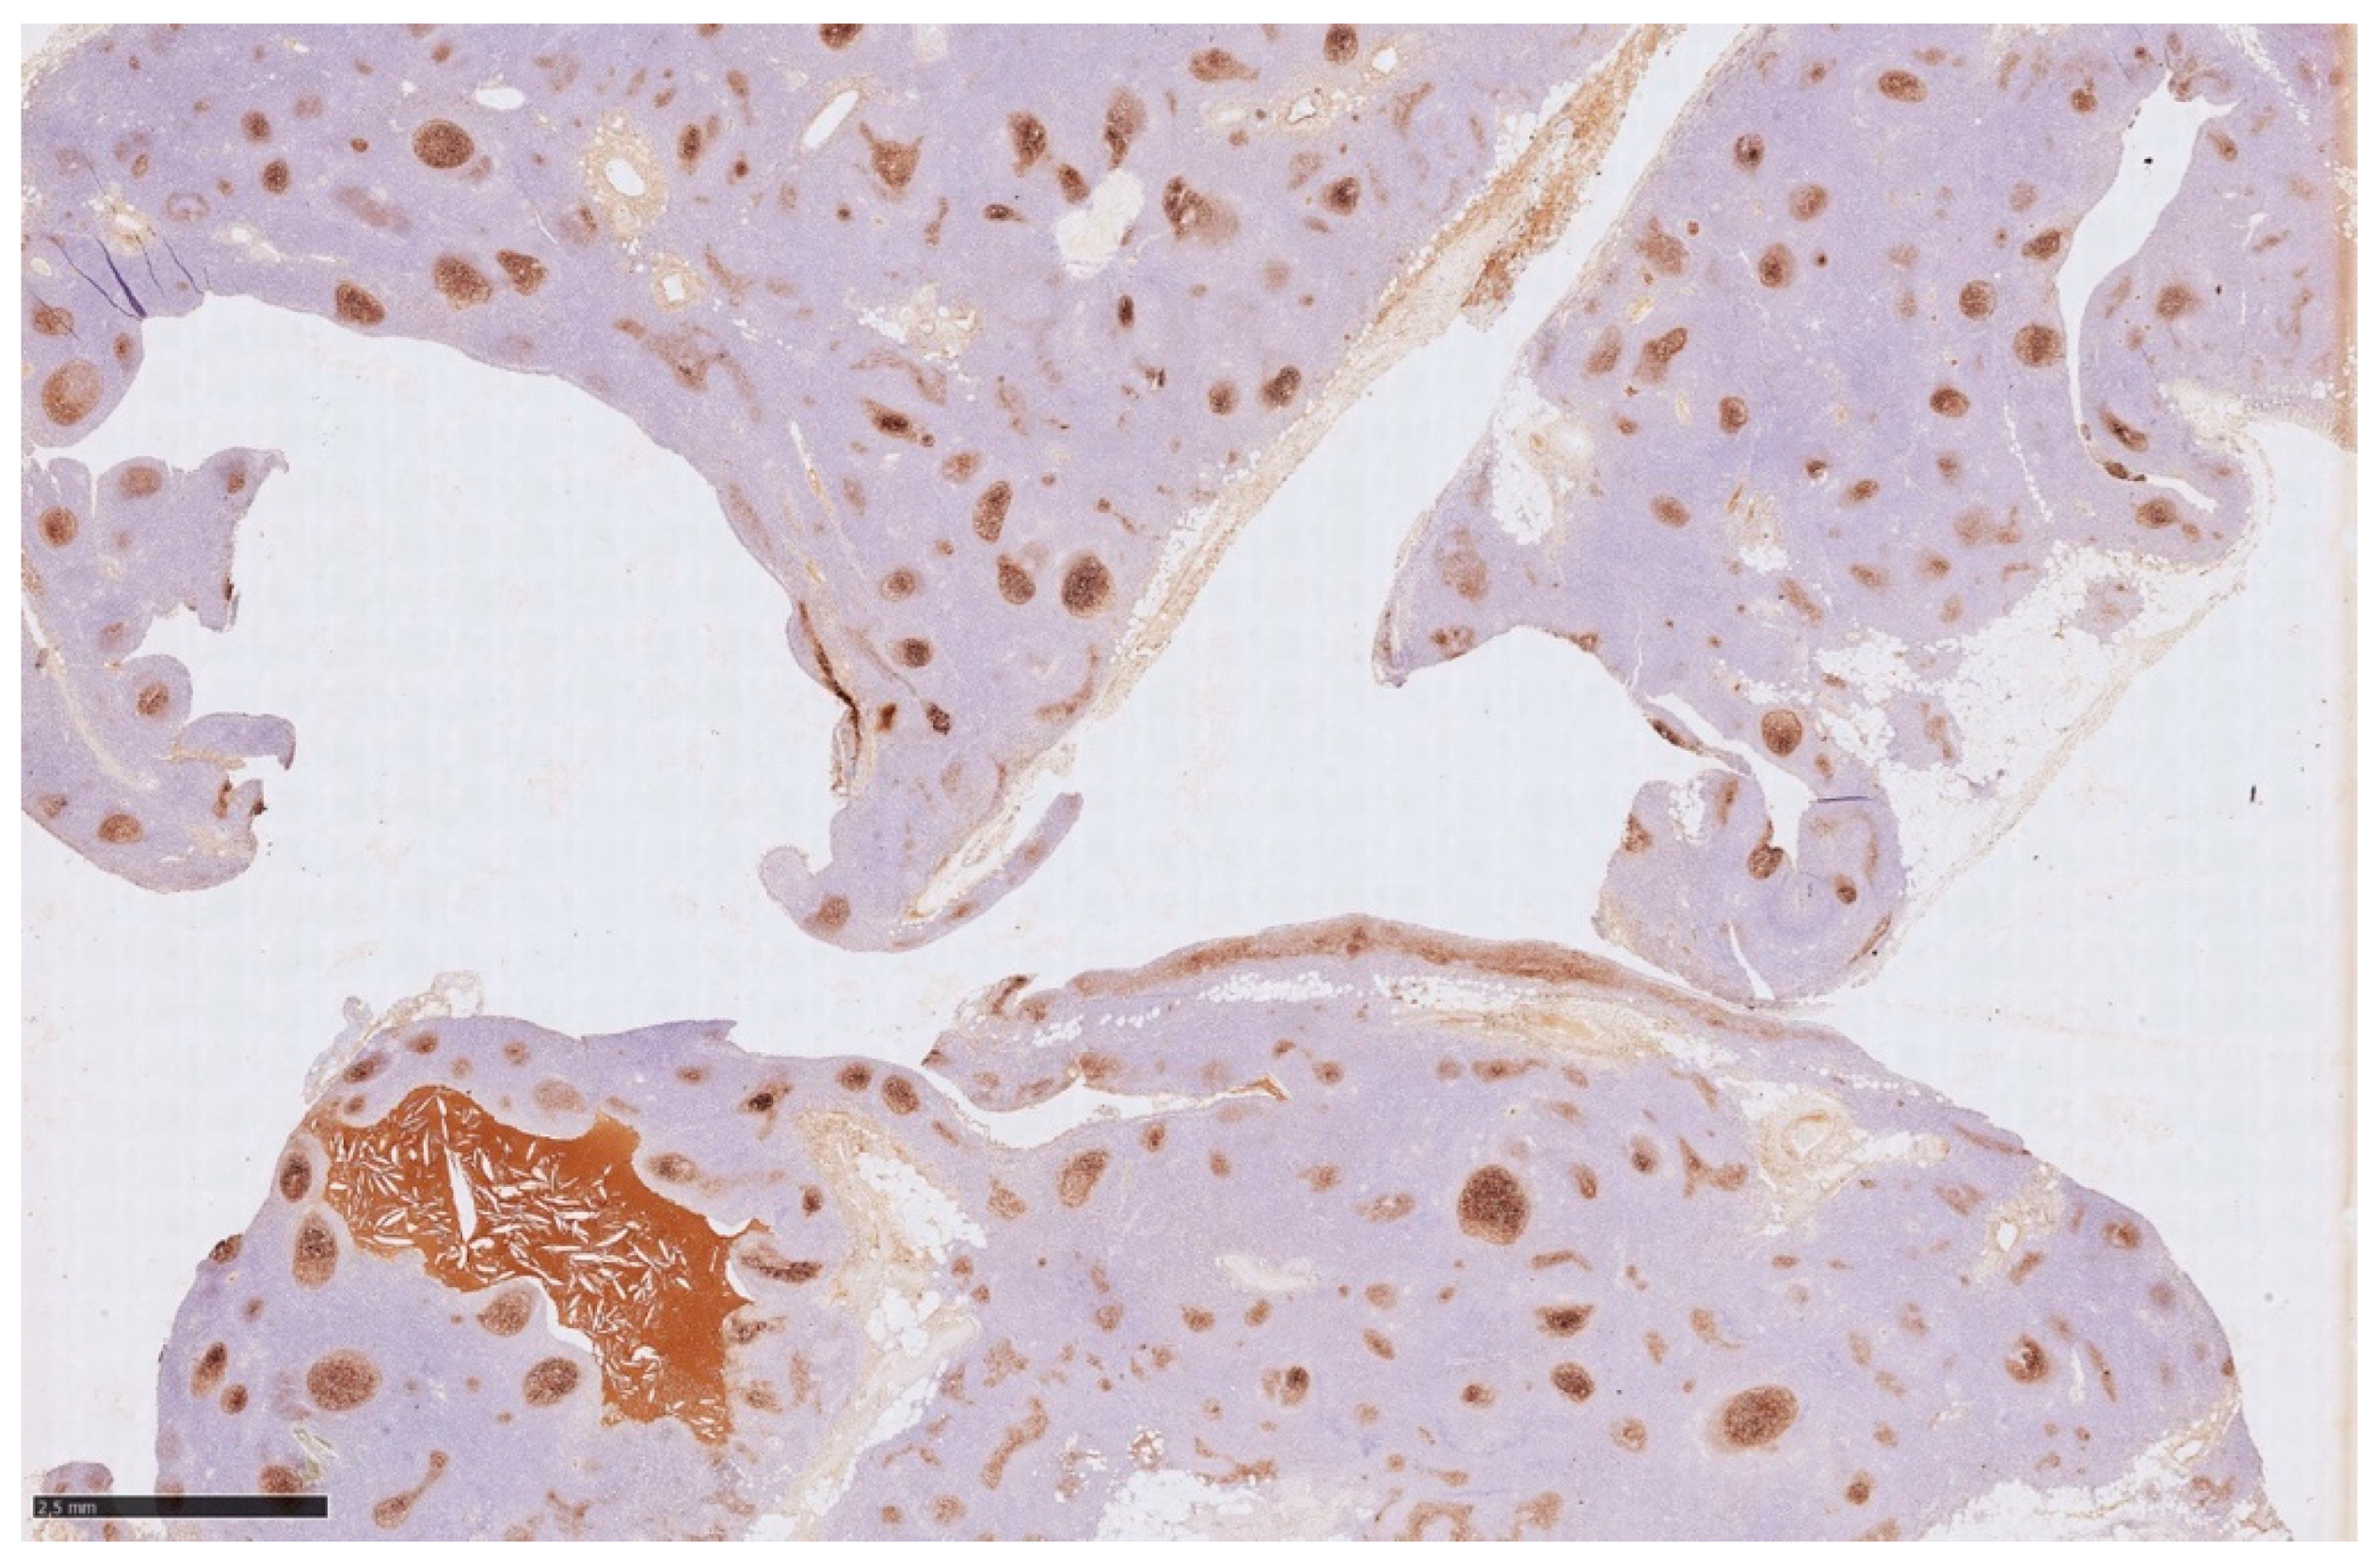

Histology showed an MTC lined by cubic epithelium and rich in lymphoid tissue, organized in germinal centers (CD10+, BCL6+, BCL2−, CD21+, CD23+), and a mantel zone (CD79A+, BCL2+), the interfollicular region represented by T-cell (CD3+), and occasional Hassall’s Corpuscles (

Figure 2,

Figure 3 and

Figure 4).